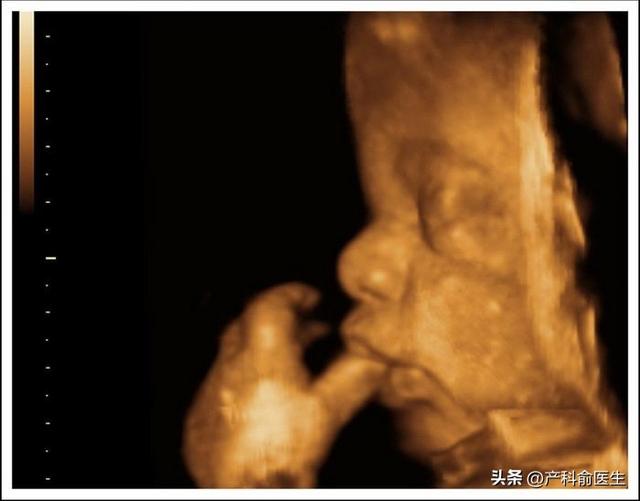

排查胎儿先天畸形;显示清晰,可以看到胎儿脸部表情、四肢动作,甚至打哈欠、伸舌头等画面。